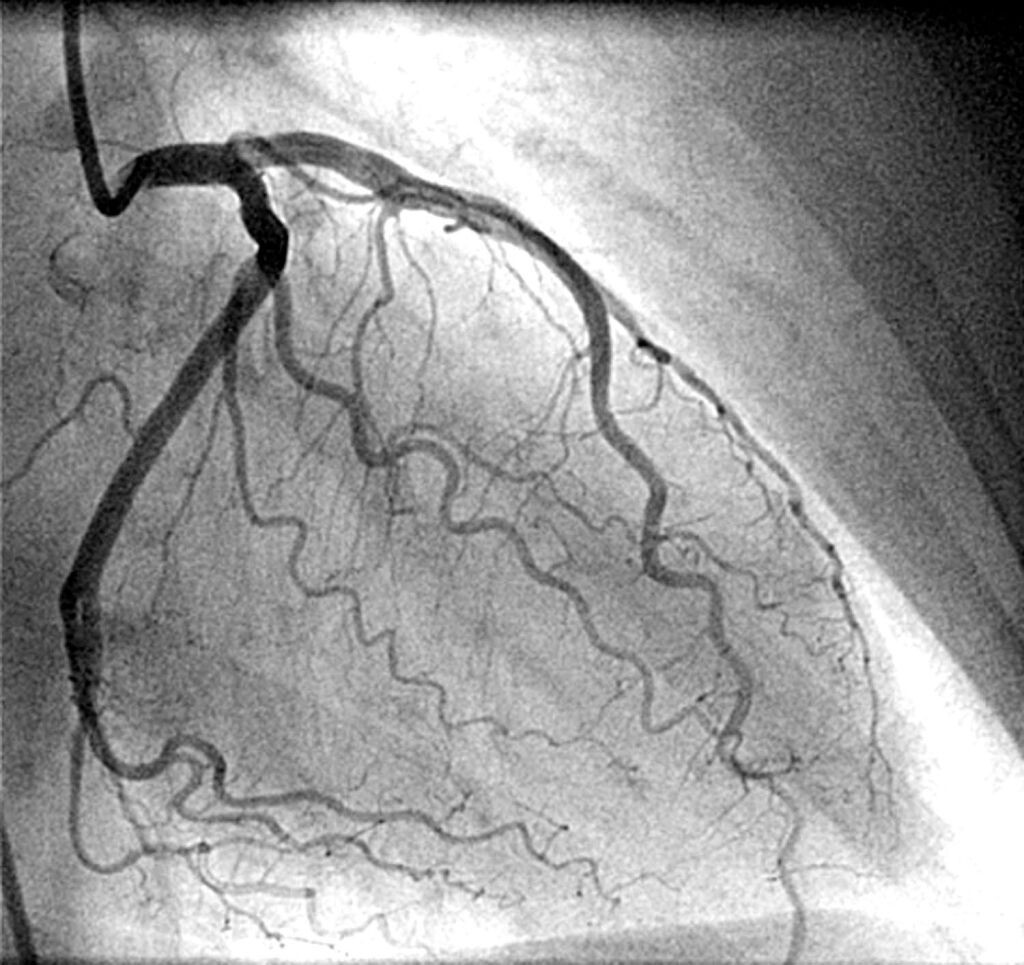

Коронарография. Через катетер вводится контрастное вещество, и сосуды сердца становятся видны на экране. Хирург точно определяет местоположение, протяжённость и степень стеноза. Это и диагностика, и навигация одновременно.